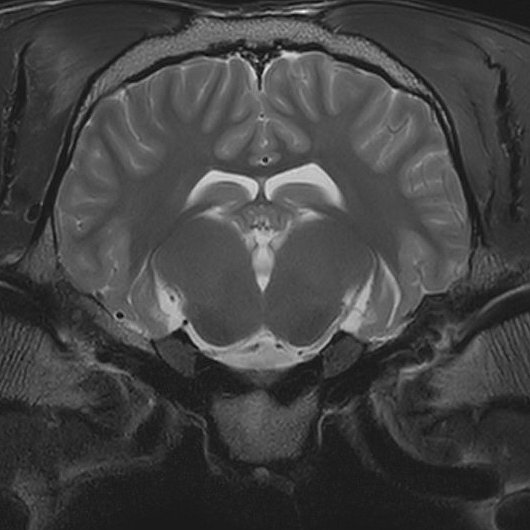

Magnetresonanztomographie - MRT

- Bei der Magnetresonanztomographie werden Schnittbilder von Organen und Gewebe durch Magnetfelder und Radiowellen gemacht. Das MRT-Gerät besteht aus einer Röhre. In dieser Röhre werden durch das Magnetfeld und die Radiowellen die Wasserstoffatome im Körper des Pferdes ausgerichtet und die Signale gemessen.

- Die Klinik für Pferde nutzt das Hochfeld MRT (3Tesla) der Kleintierklinik für die Untersuchungen. Deshalb entstehen Bilder von sehr guter Bildqualität. Allerdings ist dafür eine Narkose des Pferdes notwendig.

- Es können sowohl die Zehen, als auch Vorderfußwurzelgelenk, Sprunggelenk und das Gehirn untersucht werden.